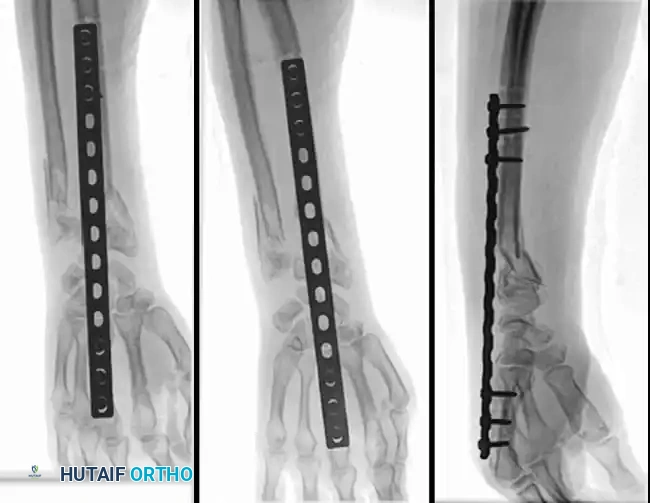

Open Reduction and Internal Fixation (ORIF)

Type II distal radial shear fractures (Barton type) usually require ORIF. These fractures are almost impossible to treat by closed means. Buttress plate fixation of volar Barton fractures is the gold standard.

Type III compression injuries require operative treatment if intraarticular damage is significant or radial shortening is severe. Careful restoration of the articular surface, radial angulation, and length is crucial. Fixation with multiple K-wires or plates is often necessary, and cancellous bone grafting is frequently required to fill impacted metaphyseal voids.

FRACTURES OF THE DISTAL RADIUS Surgical Diagram

Often, a combination of open and closed techniques is necessary to treat Type III fractures satisfactorily.

Fig. 54-103 A and B, Four-part type III distal radial fracture treated by open reduction, internal fi xation of intraarticular component, iliac bone grafting, and external fi xation. C and D, Follow-up radiographs at 5 weeks (C) and 3 years (D) show anatomical restoration of joint surface, maintenance of radial length, and absence of degenerative changes. (From Fernandez DL: Fractures of the distal radius: operative treatment, Instr Course Lect 42:73, 1993.)

Fig. 54-103 A and B, Four-part type III distal radial fracture treated by open reduction, internal fixation of intraarticular component, iliac bone grafting, and external fixation. C and D, Follow-up radiographs at 5 weeks (C) and 3 years (D) show anatomical restoration of joint surface, maintenance of radial length, and absence of degenerative changes.